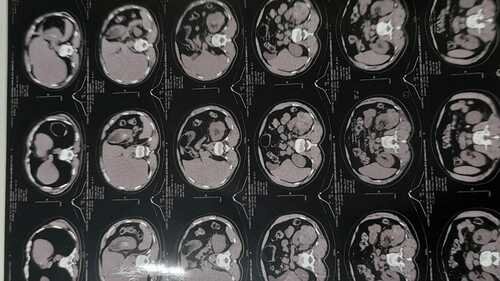

Eu sou o Antônio tenho 65 anos , morador de mogi mirim, interior de Sp! criei essa vaquinha pois preciso arrecadar 10.000,00 para retirada de uma hérnia incisional causada por retirada de tumores nos rins. Pois já aguardo a 4 anos e já sinto incômodo. Então, dependo dessa cirurgia para que eu possa retomar minhas atividades, pois dependo delas para minha sobrevivência.